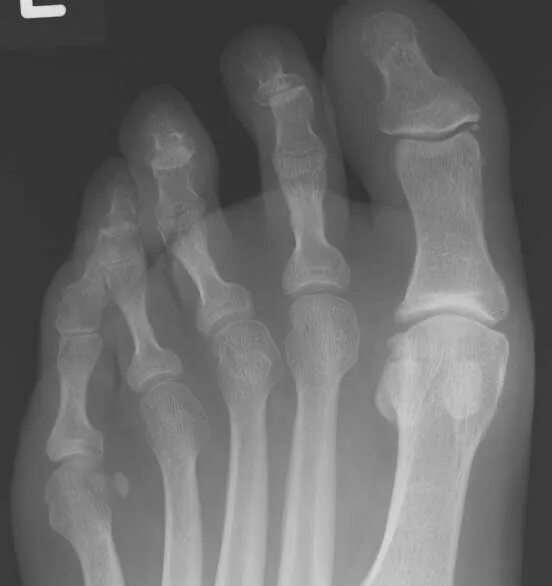

Артроз плюснефалангового сустава стопы